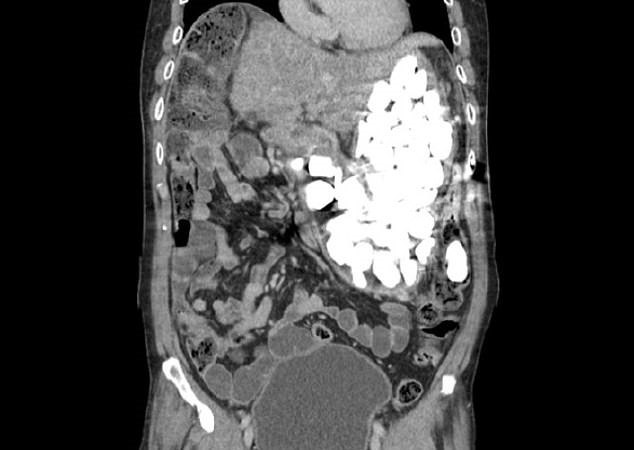

Hình ảnh chụp X-quang cho thấy có một nhóm dị vật lạ, số lượng lớn chiếm lấy toàn bộ dạ dày của bệnh nhân.

| Vật thể lạ chiếm lấy toàn bộ dạ dày của bệnh nhân. Ảnh: Dailymail. |